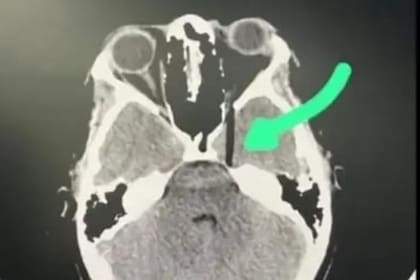

Además de estas declaraciones, también circuló una imagen correspondiente a una tomografía en donde se puede observar como se incrustó el palo en el ojo de la víctima. En redes sociales, frecuentemente aparecen recomendaciones de especialistas médicos o de pastelería que piden no realizar estas bromas, justamente por precaución de que no haya algo en el interior de la torta que actúe como soporte.